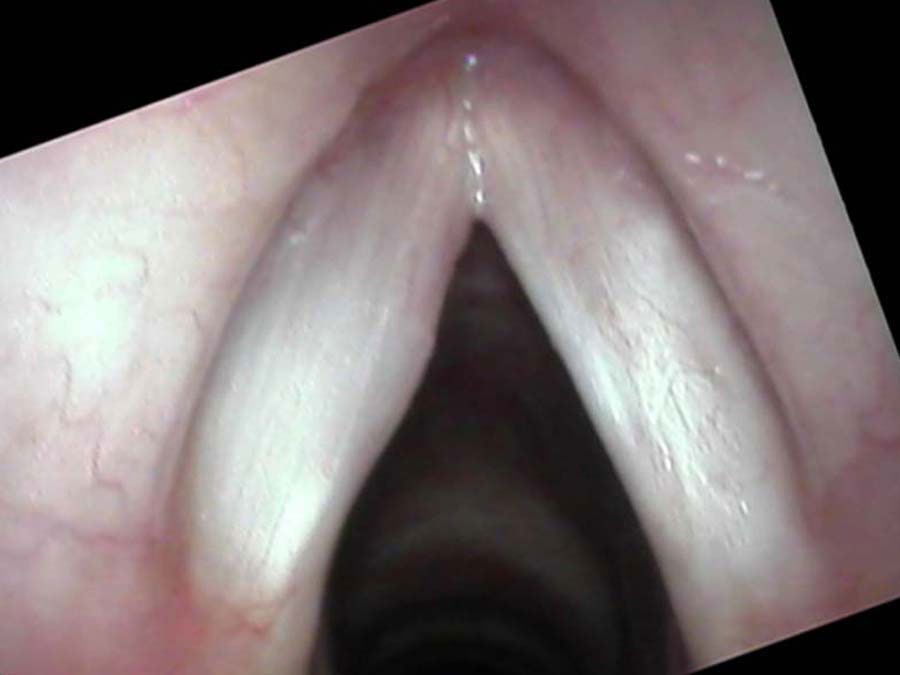

An irregular lumpy mass on the right vocal cord which is papilloma. I biopsied this in the office, to avoid using a general anesthetic in a pregnant female and confirmed it was papilloma. We then decided to wait until the end of her pregnancy to treat it. By the end of her pregnancy she was a little more short of breath and her voice was completely a whisper.

I excised visible papilloma from Darcy’s vocal cords three times. I use a CO₂ laser to cut around the edge of the papilloma and peel it off the surface of the vocal cords. It does not grow down into the vocal cords and with this technique I can best preserve the vibrations and functioning of the voice.